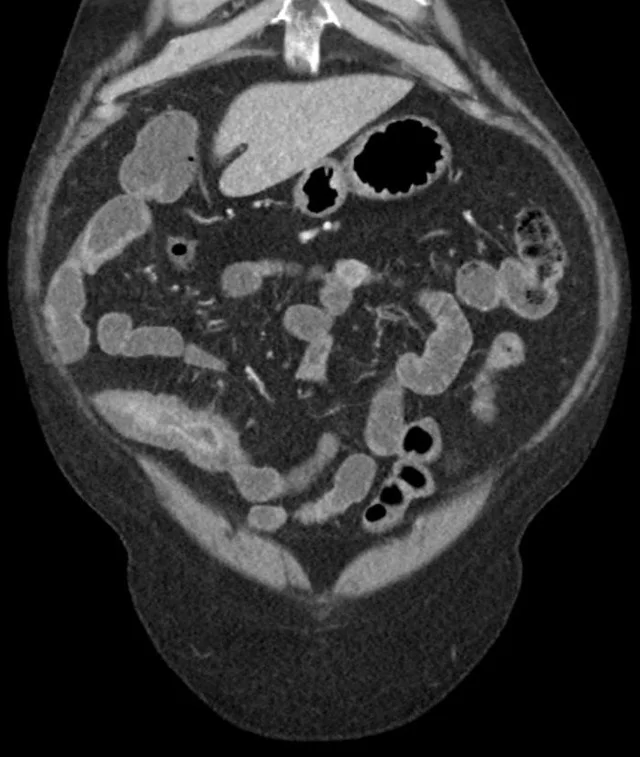

哎呀,说到克罗恩病,真是让人头疼不已!这病啊,就像个顽皮的孩子,时不时地就来捣乱一下,让人不得安宁。你知道吗,克罗恩病是一种慢性炎症性肠病,它会攻击我们的肠道,让肠道变得红肿、疼痛,甚至还会出现溃疡。这可不是什么小打小闹的病,它可是会影响到我们的饮食、生活,甚至心理健康的。

得了克罗恩病,生活简直就是一场没有硝烟的战争。每次吃饭都得小心翼翼,生怕一不小心就引发了症状。肚子疼、腹泻、体重下降,这些都成了家常便饭。有时候,真的觉得好无助,好想大喊一声:“为什么是我?”

但是,别灰心!虽然克罗恩病目前还没有根治的方法,但医学界可是在不断进步的。通过药物治疗、饮食调整、甚至是手术,我们可以有效地控制病情,减轻症状。虽然这条路可能很漫长,很艰难,但只要我们不放弃,总有一天,我们可以和这个顽皮的“孩子”和平共处。